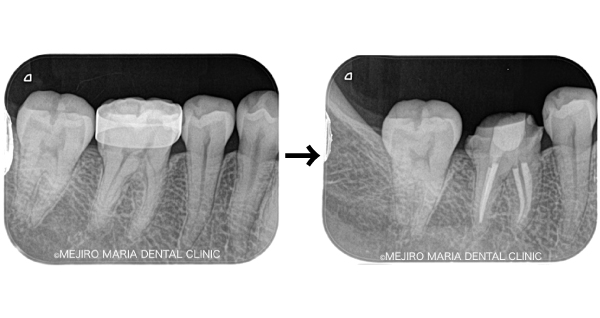

【再根管治療(感染根管治療)】

感染した歯髄や腐敗物、細菌を取り除く治療

再根管治療とは、過去に行った根管治療のやり直しを行う処置です。根尖性歯周炎の原因は根管内に潜む細菌感染ですので、根管内の細菌数を無菌的環境下で減少させ、密に封鎖することで予知性を高めることが可能です。

副作用・リスク

• 根管治療終了後には術後性疼痛がある場合があります

• 根管治療が予後不良の場合は歯根端切除術を行う必要があります